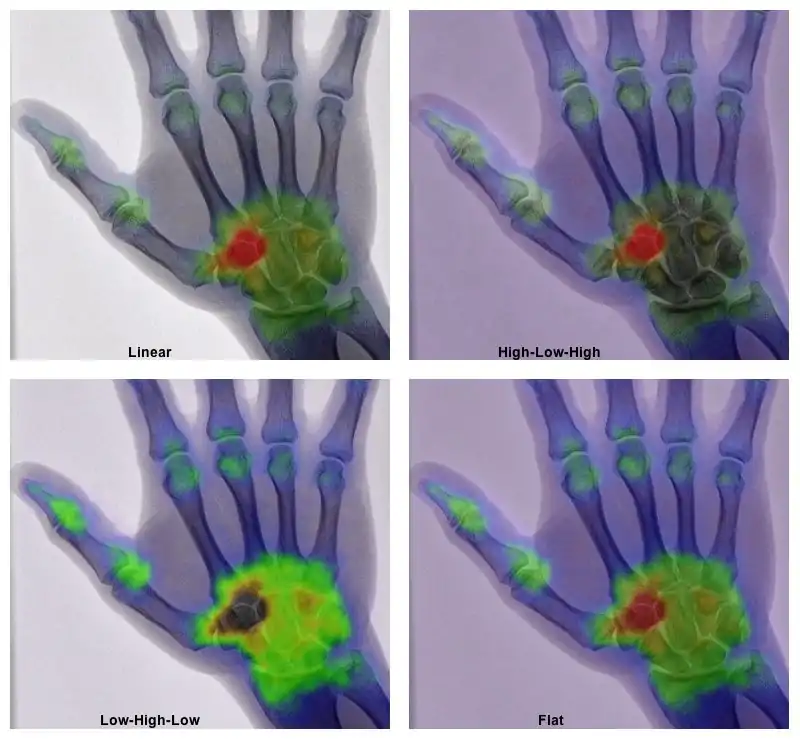

- ↑ Mettler FA Jr, Huda W, Yoshizumi TT & Mahesh M, 2008. Effective doses in radiology and diagnostic nuclear medicine: A catalog. Radiology, 248:254-63.